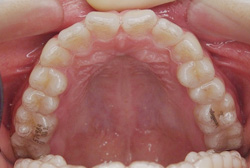

10歳8ヶ月の来院時には写真のように左右の上顎の5番目の歯が、他の歯の内側にはえています。正面から一見しては分かりませんが、内側に入っている歯が見えないため、歯が一本少なく見えています。歯を抜かずに治療を行っています。

11歳3ヶ月の写真です。○印の歯を→の方向に移動するため歯が入るようにスペースを作っています。

14歳1ヶ月の写真です。内側に入っていた5番目の歯があるべき場所に戻りました。全体の矯正治療も行っていたので、仕上がりも問題ありません。

16歳5ヶ月の写真です。あと戻りもなく非常に美しい歯並びを保てています。抜歯・非抜歯はできるだけ患者様のご要望に添えるようにしていますが、お口の中の状態や、他の歯との兼ね合いもあり抜歯をした方がより良く仕上がることも多々あります。治療方針の説明はしっかり行わせていただきますので、不安な点は歯科医師にご相談下さい。

- 治療方法

- 上顎左右第二小臼歯の口蓋側転位を伴う叢生症と診断し、固定式拡大装置(クワドヘリックス)、マルチブラケット装置にて永久歯非抜歯にて治療